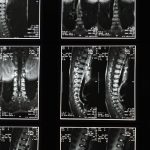

Avant de débuter la thérapie de décompression, il est essentiel de réaliser une évaluation approfondie de l’état de santé du patient. Un examen clinique, des images médicales et un historique complet des douleurs peuvent permettre de définir si ce traitement est le plus approprié en fonction des symptômes présentés.

Une IRM ou une radiographie est souvent utilisée pour confirmer le diagnostic d’un pincement discal ou d’un disque écrasé.

Une IRM ou une radiographie est souvent recommandée pour évaluer l’état de la colonne vertébrale.